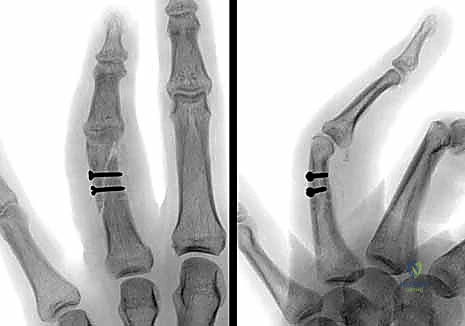

* البراغي الساحبة (Lag Screws): تُستخدم في الكسور المائلة الطويلة أو الحلزونية لتوفير ضغط قوي بين حواف الكسر.

* الصفائح والبراغي الدقيقة (Mini-plates and Screws): تُستخدم في الكسور العرضية أو المفتتة لتوفير تثبيت صلب وقوي يسمح بحركة الإصبع في اليوم التالي للعملية.